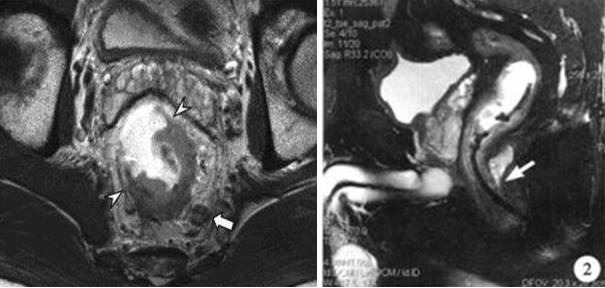

消化道疾病——肛瘘、肿瘤

直肠病变的MRI检查能够较准确的了解病变的范围,及周围有否转移侵犯,为临床提供较准确的诊断。